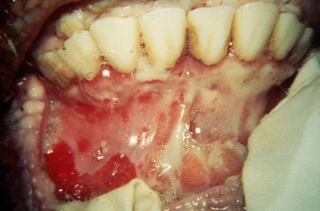

D’origine virale, c’est l’une des maladies animales les plus contagieuses pour les animaux sensibles – elle ne se transmet pas à l’Homme. © Cneva Reussir - photo archives

Plus de treize ans après sa disparition du Vieux continent, la fièvre aphteuse est de retour en Europe. Un foyer du sérotype O a été détecté en Allemagne sur des buffles d’eau à Hoppegarten, près de Berlin, ont annoncé le 10 janvier les autorités. D’origine virale, c’est l’une des maladies animales les plus contagieuses pour les animaux sensibles – elle ne se transmet pas à l’Homme. Elle touche de nombreuses espèces (bovins, ovins, caprins et porcins), d’où un impact économique qui peut être considérable. En particulier, « les porcins – notamment les sangliers – sont assez résistants à la maladie et peuvent donc la transmettre sans montrer de signes cliniques », explique David Ngwa Mbot, vétérinaire conseil à GDS France, à Agra Presse. Selon l’Agence nationale de sécurité sanitaire de l'alimentation, de l'environnement et du travail (Anses), le virus « se transmet directement d’animal à animal ou par contacts indirects » (matériel contaminé, produits animaux, interventions humaines, etc.). Alors que l’enquête épidémiologique est toujours en cours, « à ce jour, l’origine de la contamination n’est pas connue », indique la plateforme française Épidémiosurveillance en santé animale (ESA).